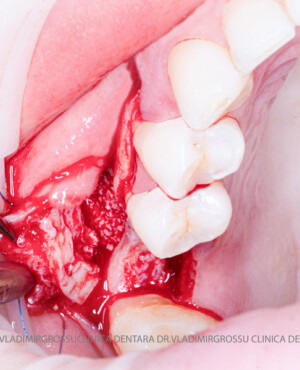

Un element esențial în procedura de aditie osoasă este utilizarea membranelor biologice, care izolează materialul osos de țesuturile moi (gingie) pe durata procesului de vindecare. Cele mai recomandate sunt membranele resorbabile din colagen sau pericard.

Adiția de gingie (gingivoplastia)

Aditia gingivală este o procedură chirurgicală ce corectează diverse probleme estetice și funcționale, cum ar fi recesiunea gingivală. În implantologia modernă, aditia de țesut moale este utilizată aproape în fiecare intervenție de inserție a implantului dentar pentru a asigura un aspect estetic natural și o bună integrare a implantului în cavitatea bucală.